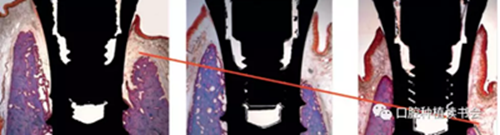

早在1976年,Schulte 教授就提出了根型種植體的巨大優(yōu)勢,根型種植體的頸部平臺更大,這樣就增加了它植入拔牙窩后的初期穩(wěn)定性,而且減少了種植體和骨板之間的間隙(圖1)。當時還認為由于根型種植體和拔牙窩的形態(tài)更匹配,有可能阻止拔牙之后唇側骨板的吸收和改變。但是,當時由于支持即刻種植的學者很少,而且缺乏短期和長期的理論文獻依據(jù),所以即刻種植技術并沒有得到迅速的推廣。

圖1最初推出的根型種植體追求與拔牙窩盡量匹配

圖2 動物實驗的病理切片顯示

即刻種植后骨板發(fā)生了顯著吸收

最初做即刻種植是為了預防牙齒拔除后牙槽窩的改建,但后來事實證明并非如此。Araújo 和 Lindhe的動物實驗表明,拔牙后3周牙槽骨板平均發(fā)生垂直吸收2.6mm。Botticelli 等獲得了類似的動物實驗研究結果,拔牙4個月后,垂直骨吸收達2.8mm(圖2),這些研究均表明牙齒拔除之后無論是否即刻種植,拔牙窩頰側、舌側骨板都會發(fā)生大量的骨改建。